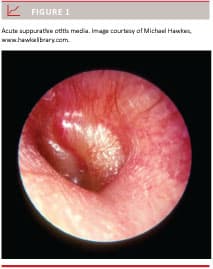

Acute otitis media (AOM) (Figure 1) is one of the most frequent paediatric diseases, but the condition may also occur among adults. Cholesteatoma is a much less common middle ear disease with onset in childhood or adulthood. Usually, the course of both AOM and cholesteatoma is benign, at least in developed countries with high socio-economic standards and easy access to health services [1]. However, due to the close anatomical proximity of the middle ear cleft and the brain, the infection can spread to intracranial structures, and otogenic meningitis or even brain abscess (BA) (Figure 2) may develop [1, 2].